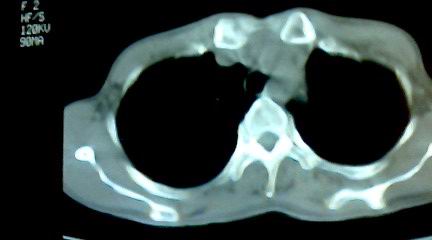

标题: CT25218:请教!胸部CT,胸8椎体骨质破坏,伴周围软组织肿。 [打印本页]

标题: CT25218:请教!胸部CT,胸8椎体骨质破坏,伴周围软组织肿。

患者,女41岁,肢体乏力。

两肺上叶继发性肺结核;胸椎结核并椎旁寒性脓肿形成。

胸椎结核并椎旁寒性脓肿形成。

恶性,椎体淋巴瘤或pnet并肺内转移。